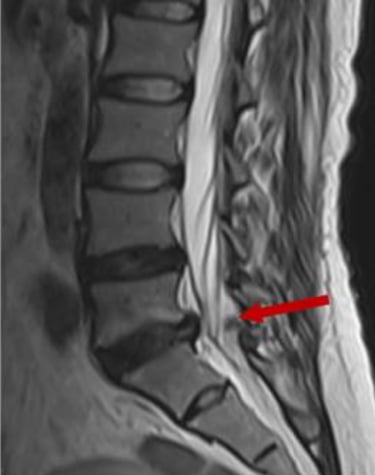

Tipo de hernia: las hernias extruidas o secuestradas (cuando el material se ha desplazado fuera del disco) tienen mayor probabilidad de reabsorción, ya que el sistema inmune puede acceder más fácilmente a ese tejido.

En cambio, las protrusiones discales (cuando el disco solo se abomba sin romperse) tienden a ser más estables y menos propensas a reabsorberse, aunque también pueden mejorar clínicamente con tratamiento conservador. El siguiente dibujo muestra la probabilidad de reabsorción según el tamaño de la hernia.